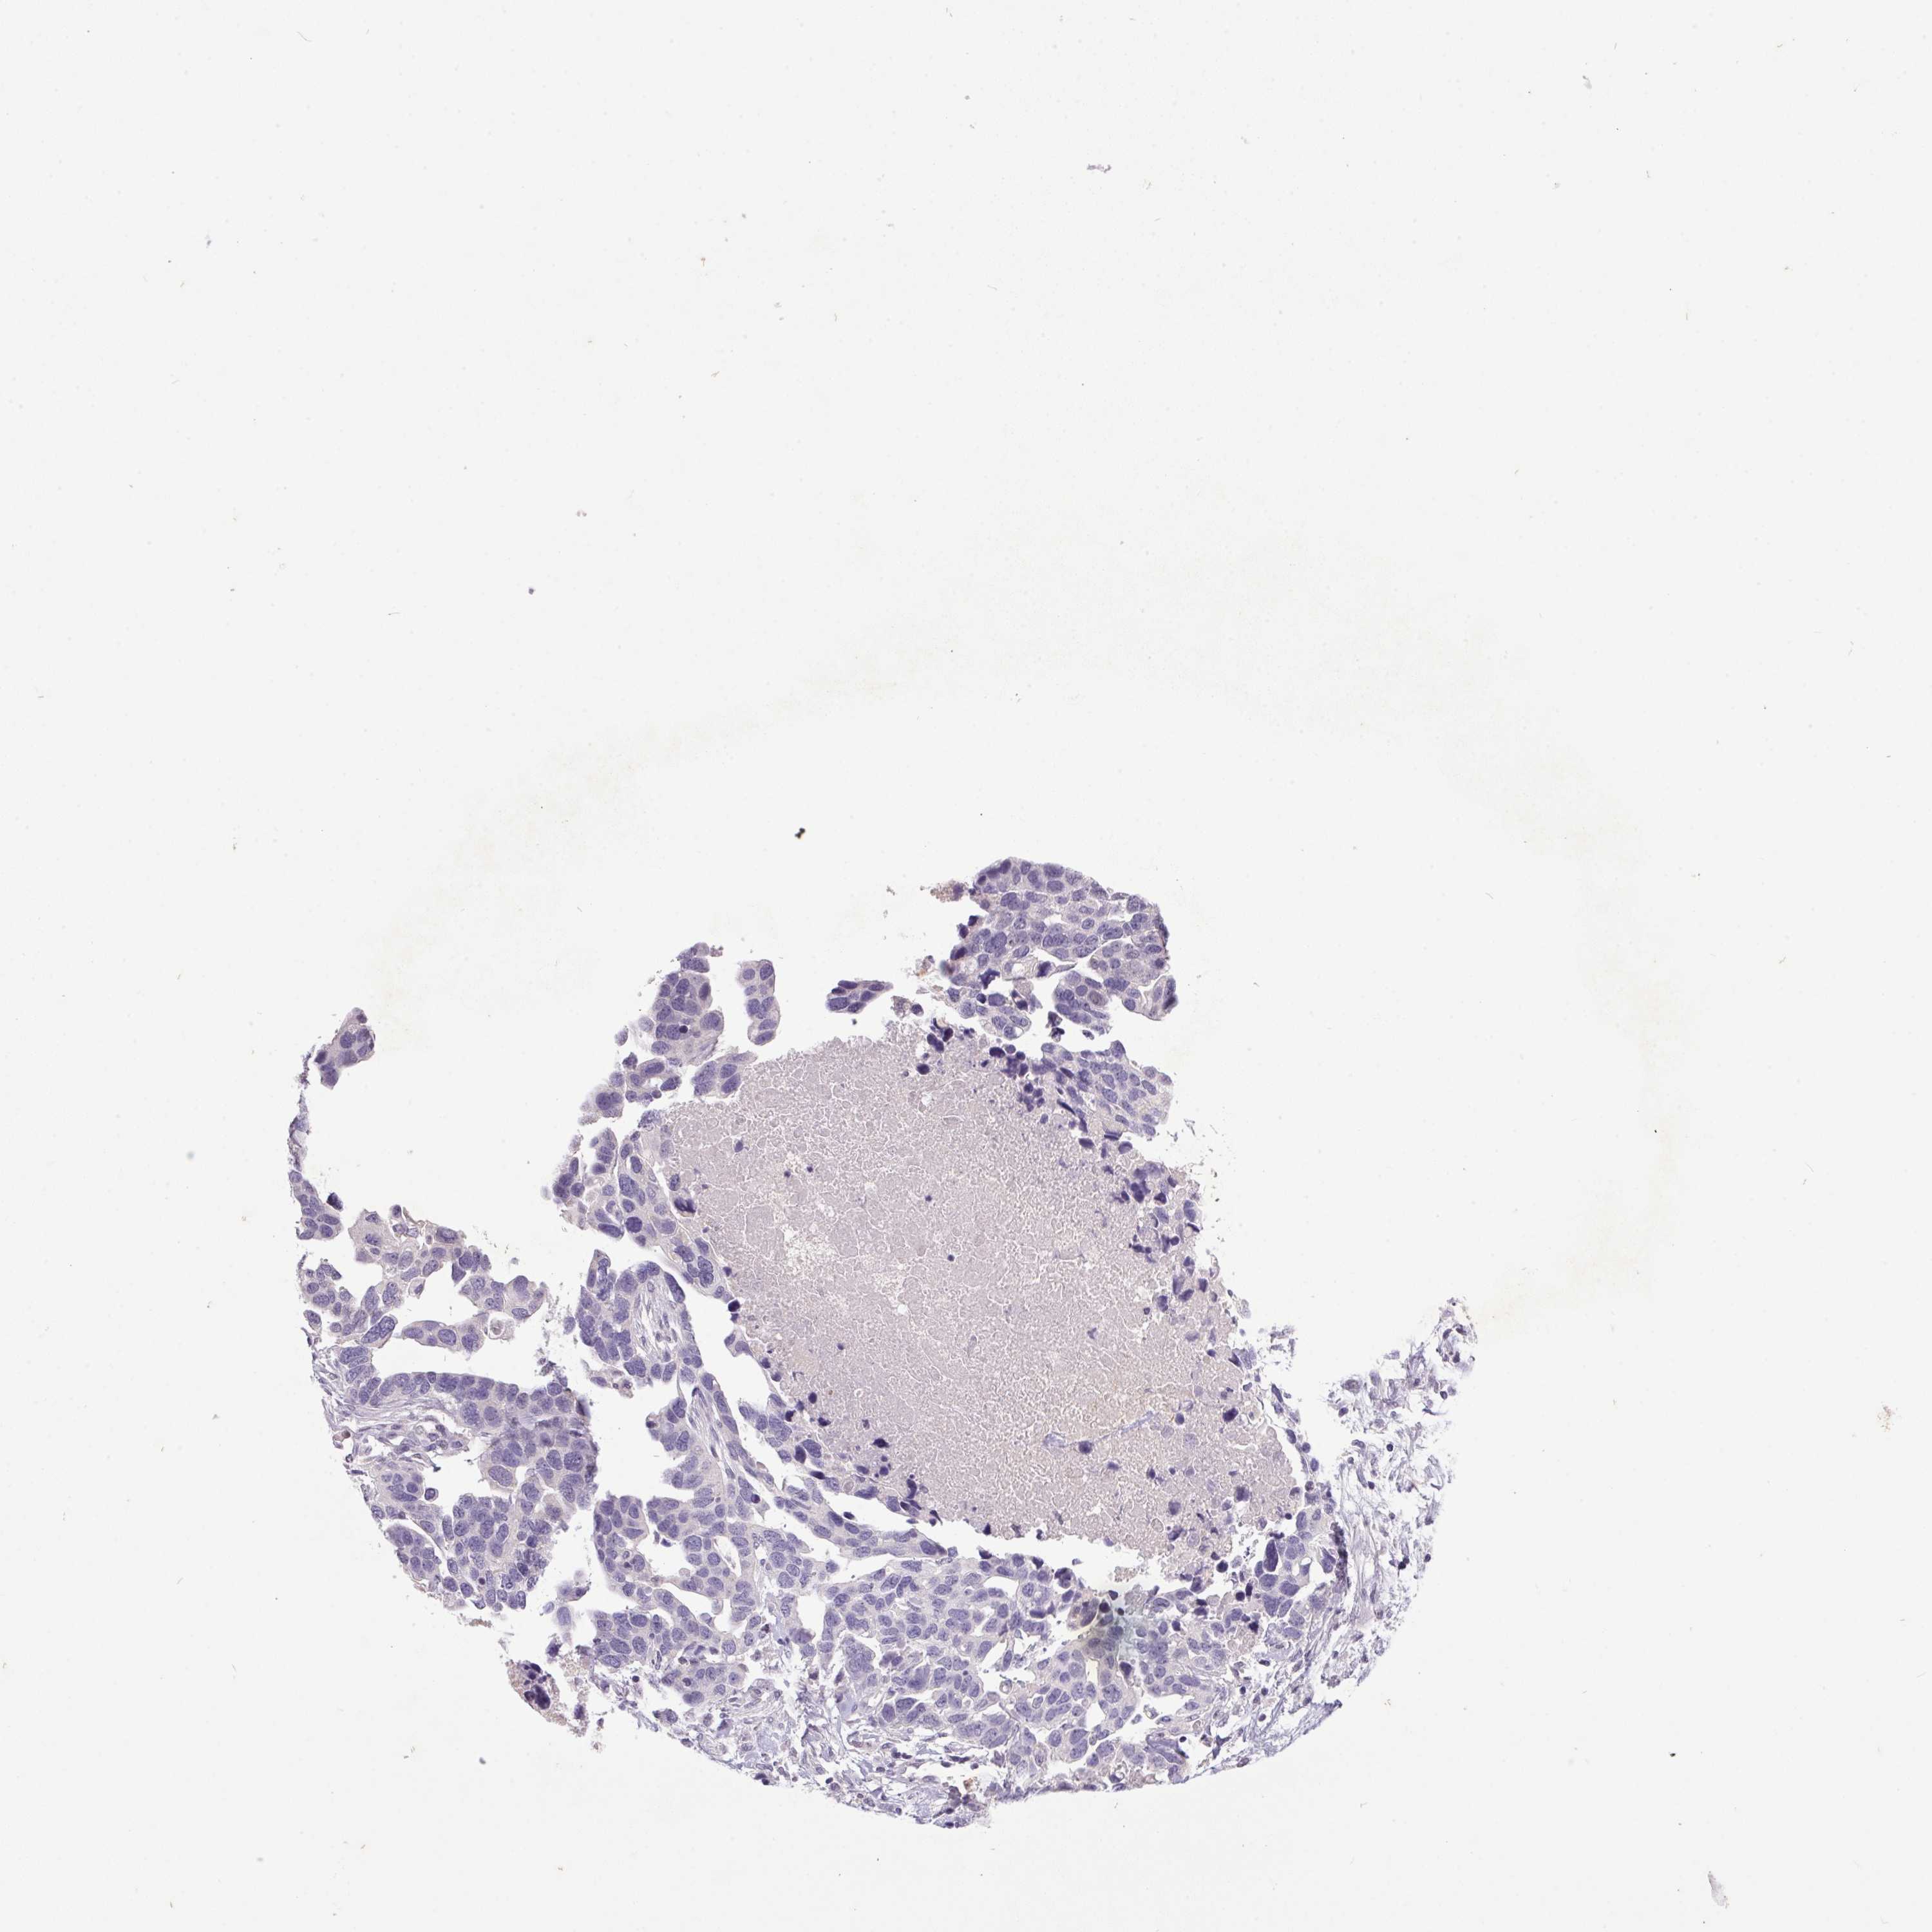

OVARIAN CANCER - Protein expressioni

A mouse-over function shows sample information and annotation data. Click on an image to view it in a full screen mode. Samples can be filtered based on level of antibody staining by selecting one or several of the following categories: high, medium, low and not detected. The assay and annotation is described here.

Note that samples used for immunohistochemistry by the Human Protein Atlas do not correspond to samples in the TCGA dataset.

Antibody stainingi

Antibody staining in the annotated cell types in the current human tissue is reported as not detected, low, medium, or high, based on conventional immunohistochemistry profiling in selected tissues. This score is based on the combination of the staining intensity and fraction of stained cells.

Each image is clickable and will lead to virtual microscopy that enables deeper exploration of all samples and also displays staining intensity scores, fraction scores and subcellular localization as well as patient and tissue information for each sample.

Antibody HPA038226

Antibody HPA058226

Cystadenocarcinoma, serous, NOS

Carcinoma, endometroid

Cystadenocarcinoma, mucinous, NOS

Carcinoma, NOS